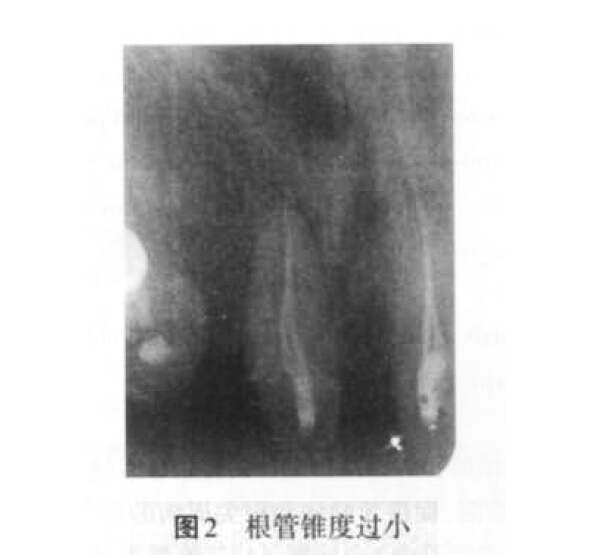

2. 1 充填不致密的原因 主要是因?yàn)楦茴A(yù)備不足、根管錐度過(guò)?。▓D2)、未根據(jù)患牙根管形態(tài)的特點(diǎn)合理選擇根充材料和技術(shù)。此外,術(shù)者操作不當(dāng)也是導(dǎo)致根充不致密的原因之一。